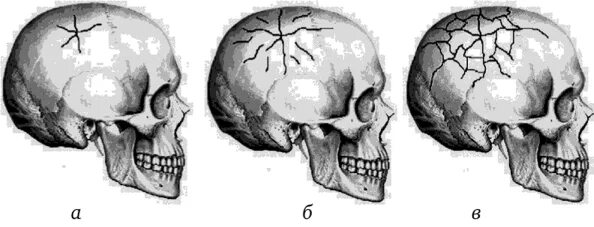

Оскольчатый перелом черепа